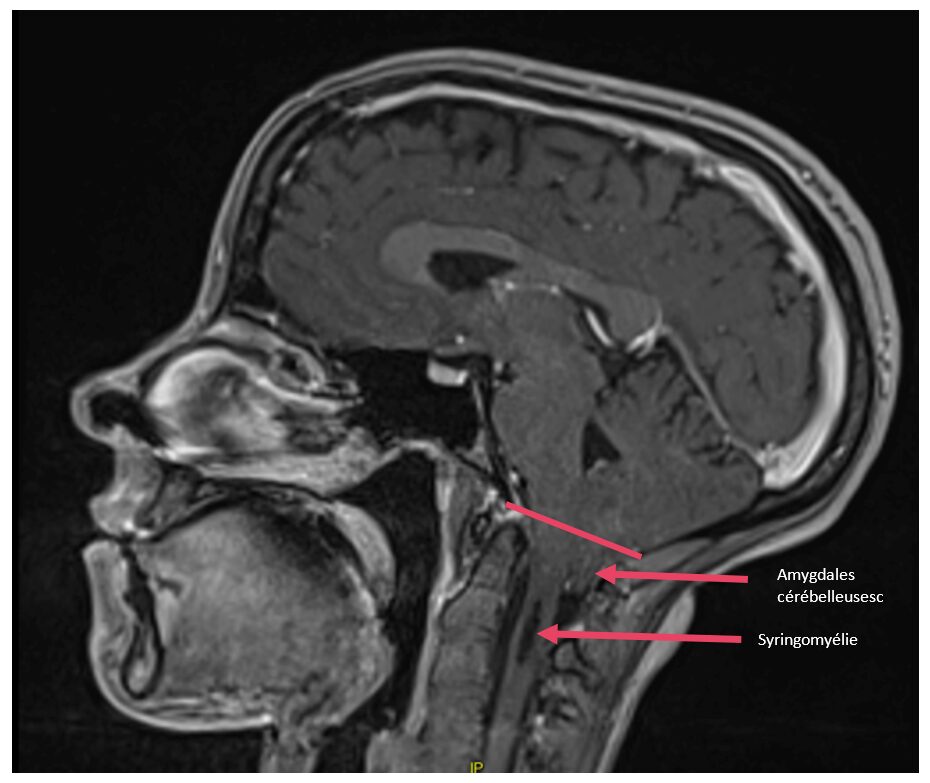

malformation d’Arnold-Chiari

Malformation d’Arnold Chiari avec syringomyélie, préopératoire

Il s’agit d’une malformation congénitale ou acquise correspondant à une anomalie de la charnière occipito-cervicale avec une descente d’une partie du cervelet dans le trou occipital (où se situe habituellement uniquement le tronc cérébral).

Celle-ci est souvent associée à des troubles de la circulation du liquide cérébro-spinal et peut aboutir à une accumulation de liquide notamment au niveau médullaire (=syringomyélie).